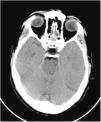

This was a 61-year-old male with no previous medical history, not vaccinated against SARS-CoV-2, who of his own free will began to consume chlorine dioxide daily in the belief that it would prevent the infection. After two weeks he developed gradual-onset encephalopathy symptoms with bradypsychia, derealisation, irritability and anxiety. Physical examination revealed dehydration of skin and mucosa. Brain computed tomography (CT) revealed cerebral oedema and idiopathic intracranial hypertension (Fig. 1). Fundus examination and lumbar puncture were normal. Blood tests showed: sodium 112 mEq/l; chlorine 77 mEq/l; plasma osmolarity 230 mOsm/kg; and uric acid 2.2 mg/dl; and fractional excretion of uric acid (FEUa) on admission was 15.4% and after 72 h with normalisation of natraemia, 11.4%. Venous blood gases: pH 7.42, bicarbonate (HCO3) 21 mmol/l, CO2 42 mmHg. No other findings of note. Urinalysis: sodium 72 mEq/l, potassium 30 mEq/l, chlorine 55 mEq/l, uric acid 15.4 mg/dl and osmolarity 224 mOsm/kg. The chlorine dioxide was immediately discontinued and treatment was started for water and electrolyte replacement progressively according to sodium deficit, with gradual restoration of neurological status and return to normal of analytical parameters (Table 1). A differential diagnosis of “other possible causes of hyponatraemia” was made.